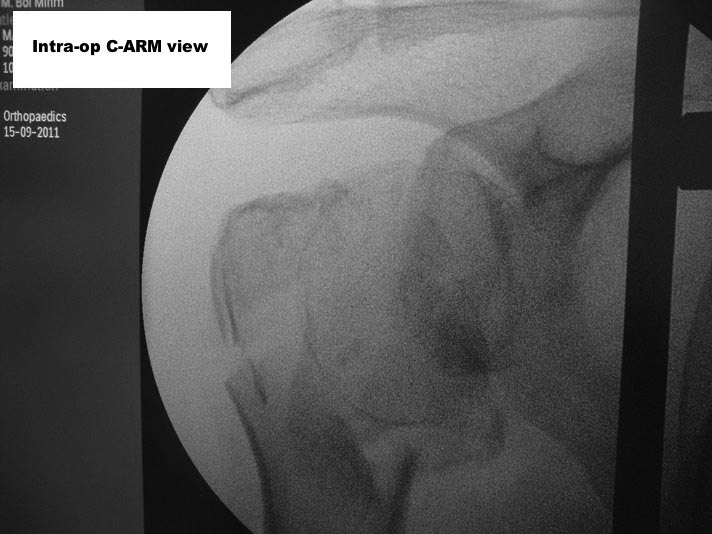

Here are some photos, of chronic, locked, 4 part posterior dislocation, 2 months old, that I did September/2011. Patient is 67, very, very active - had a really reasonable, honest clinical result ...

Photos attached ...

Пошли на операцию, будучи готовыми как к фиксации, так и к протезированию. Головка с краев была неполная, но для двух винтов места хватило. Сделали что-то вроде гемиартропластики собственной головкой. Бугорки фиксировали, как при эндопротезировании.

Снимки вот.